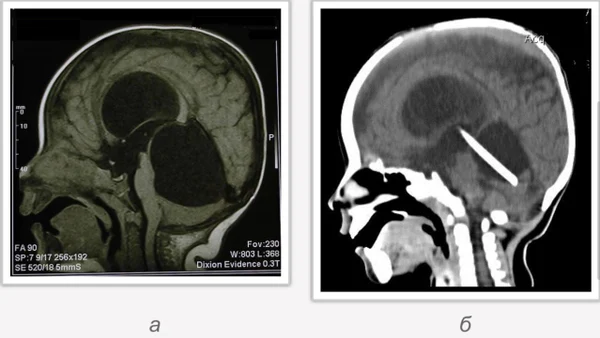

кисты, аномалии Денди-Уокера и др.Операции при внутричерепных кистах. В основном встречаются арахноидальные кисты различных локализаций и кисты сосудистых сплетений боковых желудочков. Пациентам с врождёнными кистами операции проводятся в следующих ситуациях: увеличении объема кисты в динамике, наличии клинических проявлений, компрессии и дислокации мозговых структур, наличии окклюзии ликворных путей. Нами используются 2 способа хирургического лечения кист: эндоскопическая перфорация стенок кист и открытая резекция кист. Открытая резекция кист проводится при ретроцеребеллярных арахноидальных кистах (рис. 2), при арахноидальных кистах межполушарной щели при отсутствии непосредственного контакта их стенок со стенками расширенных желудочков головного мозга и повторного увеличения кист средней черепной ямки после эндоскопической кисто-цистерностомии. Техника операции заключается в проведение краниотомии и максимальном иссечении стенок кист с созданием широкого сообщения кист с субарахноидальным пространством. Эндоскопические операции проводятся при арахноидальных кистах межножковой и пинеальной цистерн, арахноидальных кистах межполушарной щели при тесном контакте их стенок со стенками расширенной желудочковой системы (рис. 3), первично при арахноидальных кистах средней черепной ямки, а также при кистах сосудистых сплетений боковых желудочков. При арахноидальных кистах межножковой цистерны эндоскопически проводится перфорация стенок кисты, сообщая ее с просветом III желудочка и межножковой цистерной – эндоскопическая вентрикуло-кисто-цистерностомия (рис. 4). При арахноидальных кистах пинеальной цистерны проводится перфорация кисты в передне-верхних её отделах с созданием сообщения полости кисты с просветом III желудочка – эндоскопическая кисто-вентрикулостомия. С целью предотвращения облитерации сформированного отверстия иногда в полость кисты под контролем эндоскопа вводится стент перфорированный на протяжении (рис. 5, 6). Эндоскопическая кисто-цистерностомия выполняется при арахноидальных кистах средней черепной ямки. При этом создается широкое сообщение кисты с базальными цистернами. При кистах сосудистых сплетений боковых желудочков проводится их вскрытие в просвет боковых желудочков – эндоскопическая кисто-вентрикулостомия. При множественных кистах проводится их хирургическое сообщение между собой – интеркистосмия